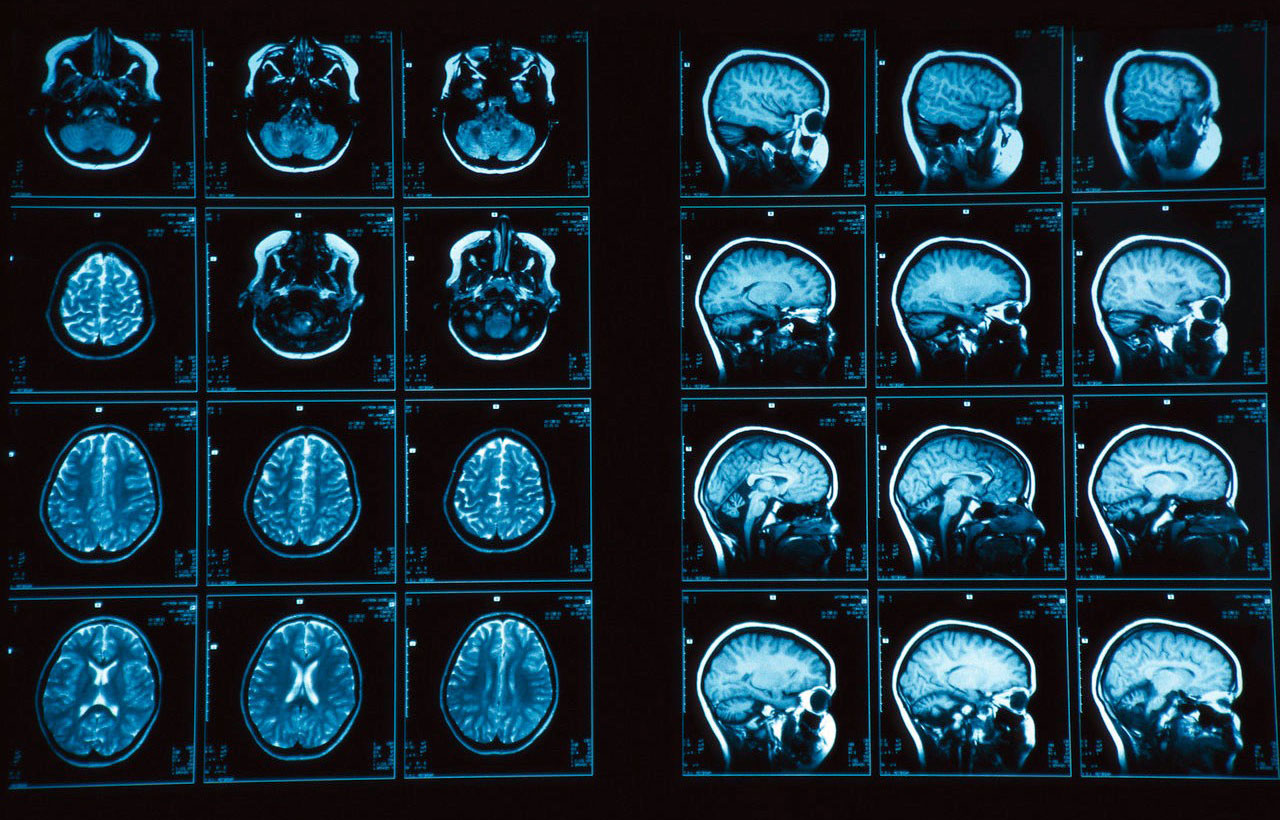

Я проконсультировался с врачом, несколько лет отработавшим в отделении нейрохирургии одной из московских больниц, и он воздержался от радикальной оценки ситуации из-за крайне малого количества информации в случае с Кейвом. Но предположил, что у парня была киста сосудистого сплетения, которая может образоваться в любом возрасте вследствие многочисленных стрессов, хронического переутомления, сильного переохлаждения организма и т.д. Симптоматика в таком случае проявляется редко, но образование можно было обнаружить с помощью обычного МРТ головного мозга.

Нельзя сказать, что это исследование регулярно назначают всем подряд. Даже люди, у которых были диагностированы какие-то проблемы, делают МРТ не чаще раза в год. Поэтому можно легко предположить, что на медосмотре в клубах НХЛ эту процедуру проходят только те, у кого есть какие-либо жалобы: головокружения, боли, проблемы с координацией или зрением, эпилептические припадки и т.д.

У парня было все нормально, но есть очень важный вопрос: "Проходил ли Кейв обследование после той драки с Поспишилом?". Тогда он получил несколько серьезных ударов по голове, которые могли быть опасны для его здоровья. То есть, в теории Колби после того эпизода могли направить на МРТ головного мозга, чтобы исключить неблагоприятные последствия вроде сотрясения или гематомы, которая может привести к отеку. А могли просто посветить фонариком в глаз, проверить реакцию зрачка и спросить: "Ты в порядке, парень?".

Учитывая, что Кейв попал в больницу с кровоизлиянием в мозг, можно предположить, что размер кисты достиг серьезных размеров – более 15 мм. Динамика ее роста всегда индивидуальна, но можно предположить, что это образование можно было увидеть на МРТ после той драки с Поспишилом, если бы оно, конечно, проводилось.